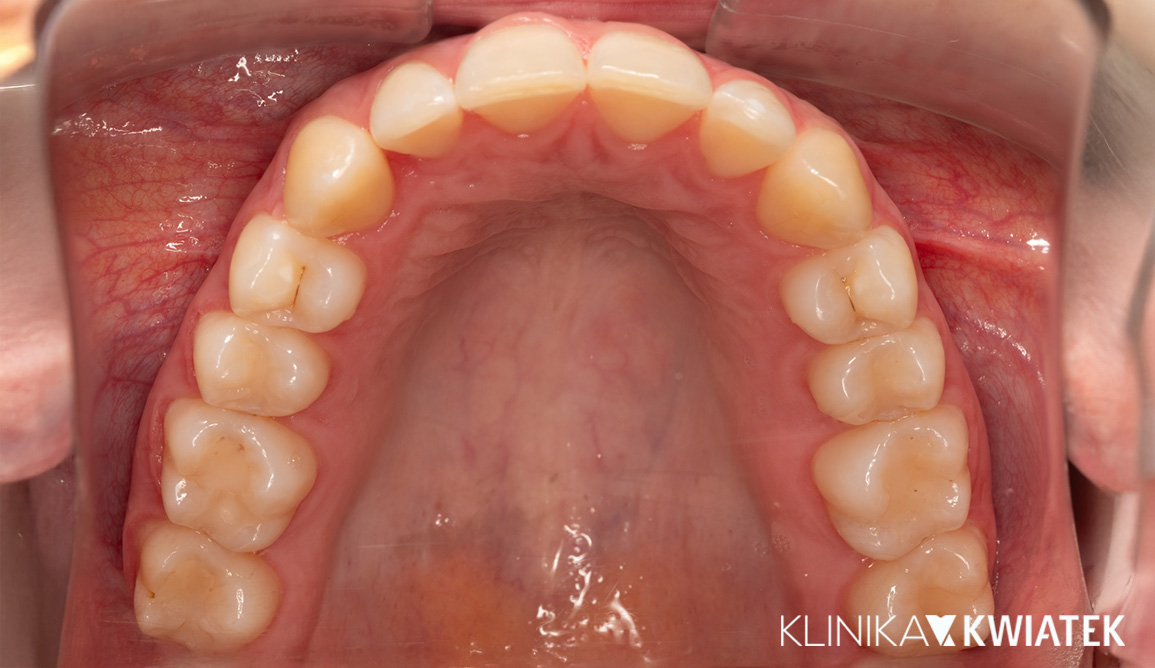

Kompleksowa metamorfoza uśmiechu – od ortodoncji po protetykę i implantologię

Pacjent zgłosił się do kliniki z problemem przetrwałych zębów mlecznych, diastemy i nierównego zgryzu, oczekując szybkiego, ale trwałego efektu estetycznego. Przeprowadzono wieloetapowe leczenie obejmujące higienizację, leczenie zachowawcze, terapię nakładkami ortodontycznymi, implantację oraz nowoczesną protetykę. Finalnym efektem jest harmonijny, biały i zdrowy uśmiech, dopasowany do rysów twarzy.